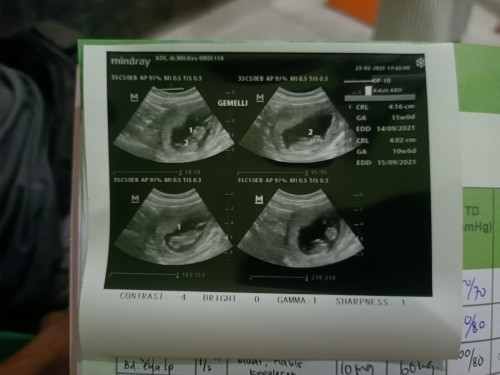

Sharing yuk bund.. saya baru menikah november lalu skrg saya sedang hamil. Pertama kali hamil pas usg 5week dokternya nyeletuk bilang siapa tau kembar. Saya pikir cuma bercanda. Terus kmrn saya inisiatif usg lagi pas 11 week dan dokternya bilang kembar. Saya dan suami auto shock bun karna ini kehamilan pertama saya. Adakah bumil yg baru menikah hamil anak kembar juga? Apa vitamin hamil tunggal dan hamil kembar beda? Kalo iya bagusnya minum vitamin apa ya bund? #seriusnanya #bantusharing #firstbaby #jangandibully